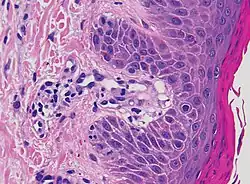

| Lichen planus | Irregular epidermal hyperplasia with a jagged “sawtooth” appearance, compact hyperkeratosis or orthokeratosis, foci of wedge-shaped hypergranulosis, basilar vacuolar degeneration, slight spongiosis in the spinous layer, and squamatization. The dermal papillae between the elongated rete ridges are frequently dome shaped. Necrotic keratinocytes can be observed in the basal layer of the epidermis and at the dermal-epidermal junction. Eosinophilic remnants of anucleate apoptotic basal cells may also be found in the dermis and are referred to as “colloid or civatte bodies”. Whickham striae are usually seen in the areas of hypergranulosis. Vacuolar degeneration at the basal layer may be noted leading to focal subepidermal clefts (Max Joseph spaces). Squamatization occurs as a result of maturation and flattening of cells in the basal layer. It happens in areas of marked hypergranulosis with prominence of the sawtooth pattern of rete ridges. Wedge-shaped hypergranulosis can occur in the eccrine ducts (acrosyringia) or hair follicles (acrotrichia). In the hypertrophic subtype, the associated hyperkeratosis, parakeratosis, hypergranulosis, papillomatosis, acanthosis, and hyperplasia markedly increased with thicker collagen bundles forming in the dermis. Moreover, the rete ridges are more elongated and rounded as opposed to the typical sawtooth pattern. In atrophic LP, loss of the rete ridges and dermal fibrosis is prominent. In vesiculobullous LP, the disease progression is quicker. Hence, some of the distinctive features such as hyperkeratosis, hypergranulosis, or dense lymphocytic dermal-epidermal infiltrate may not be present. LP lesion may resolve with residual hyperpigmentation caused by a persistent increase in the number of melanophages in the papillary dermis.[9] | ![]() |